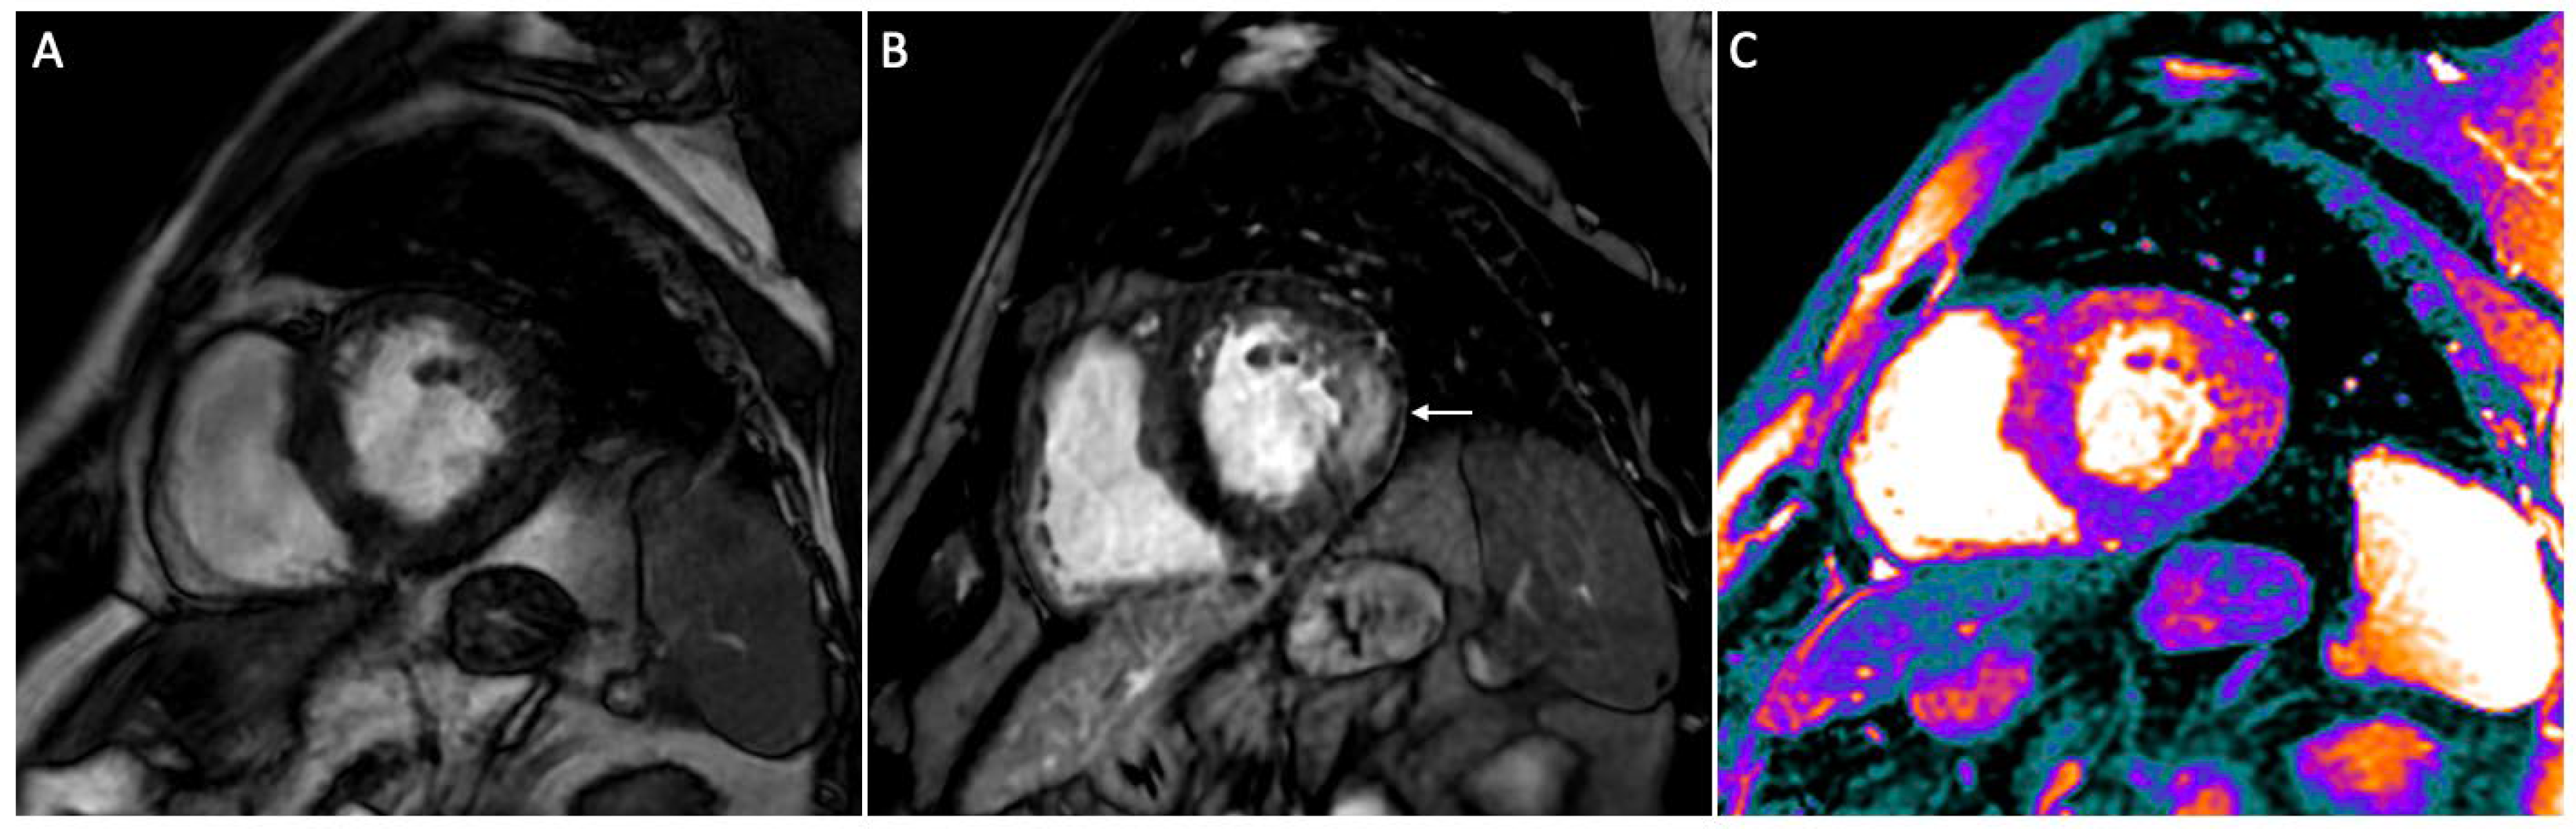

| Imbriaco [58] | 2019 | Effect of ERT on myocardial storage, inflammation, and hypertrophy | Prospective, single-center | 20 AFD; 7 controls | Patients with COV >0.17 had higher T1 values in the lateral LV wall compared to those with COV ≤0.17 |